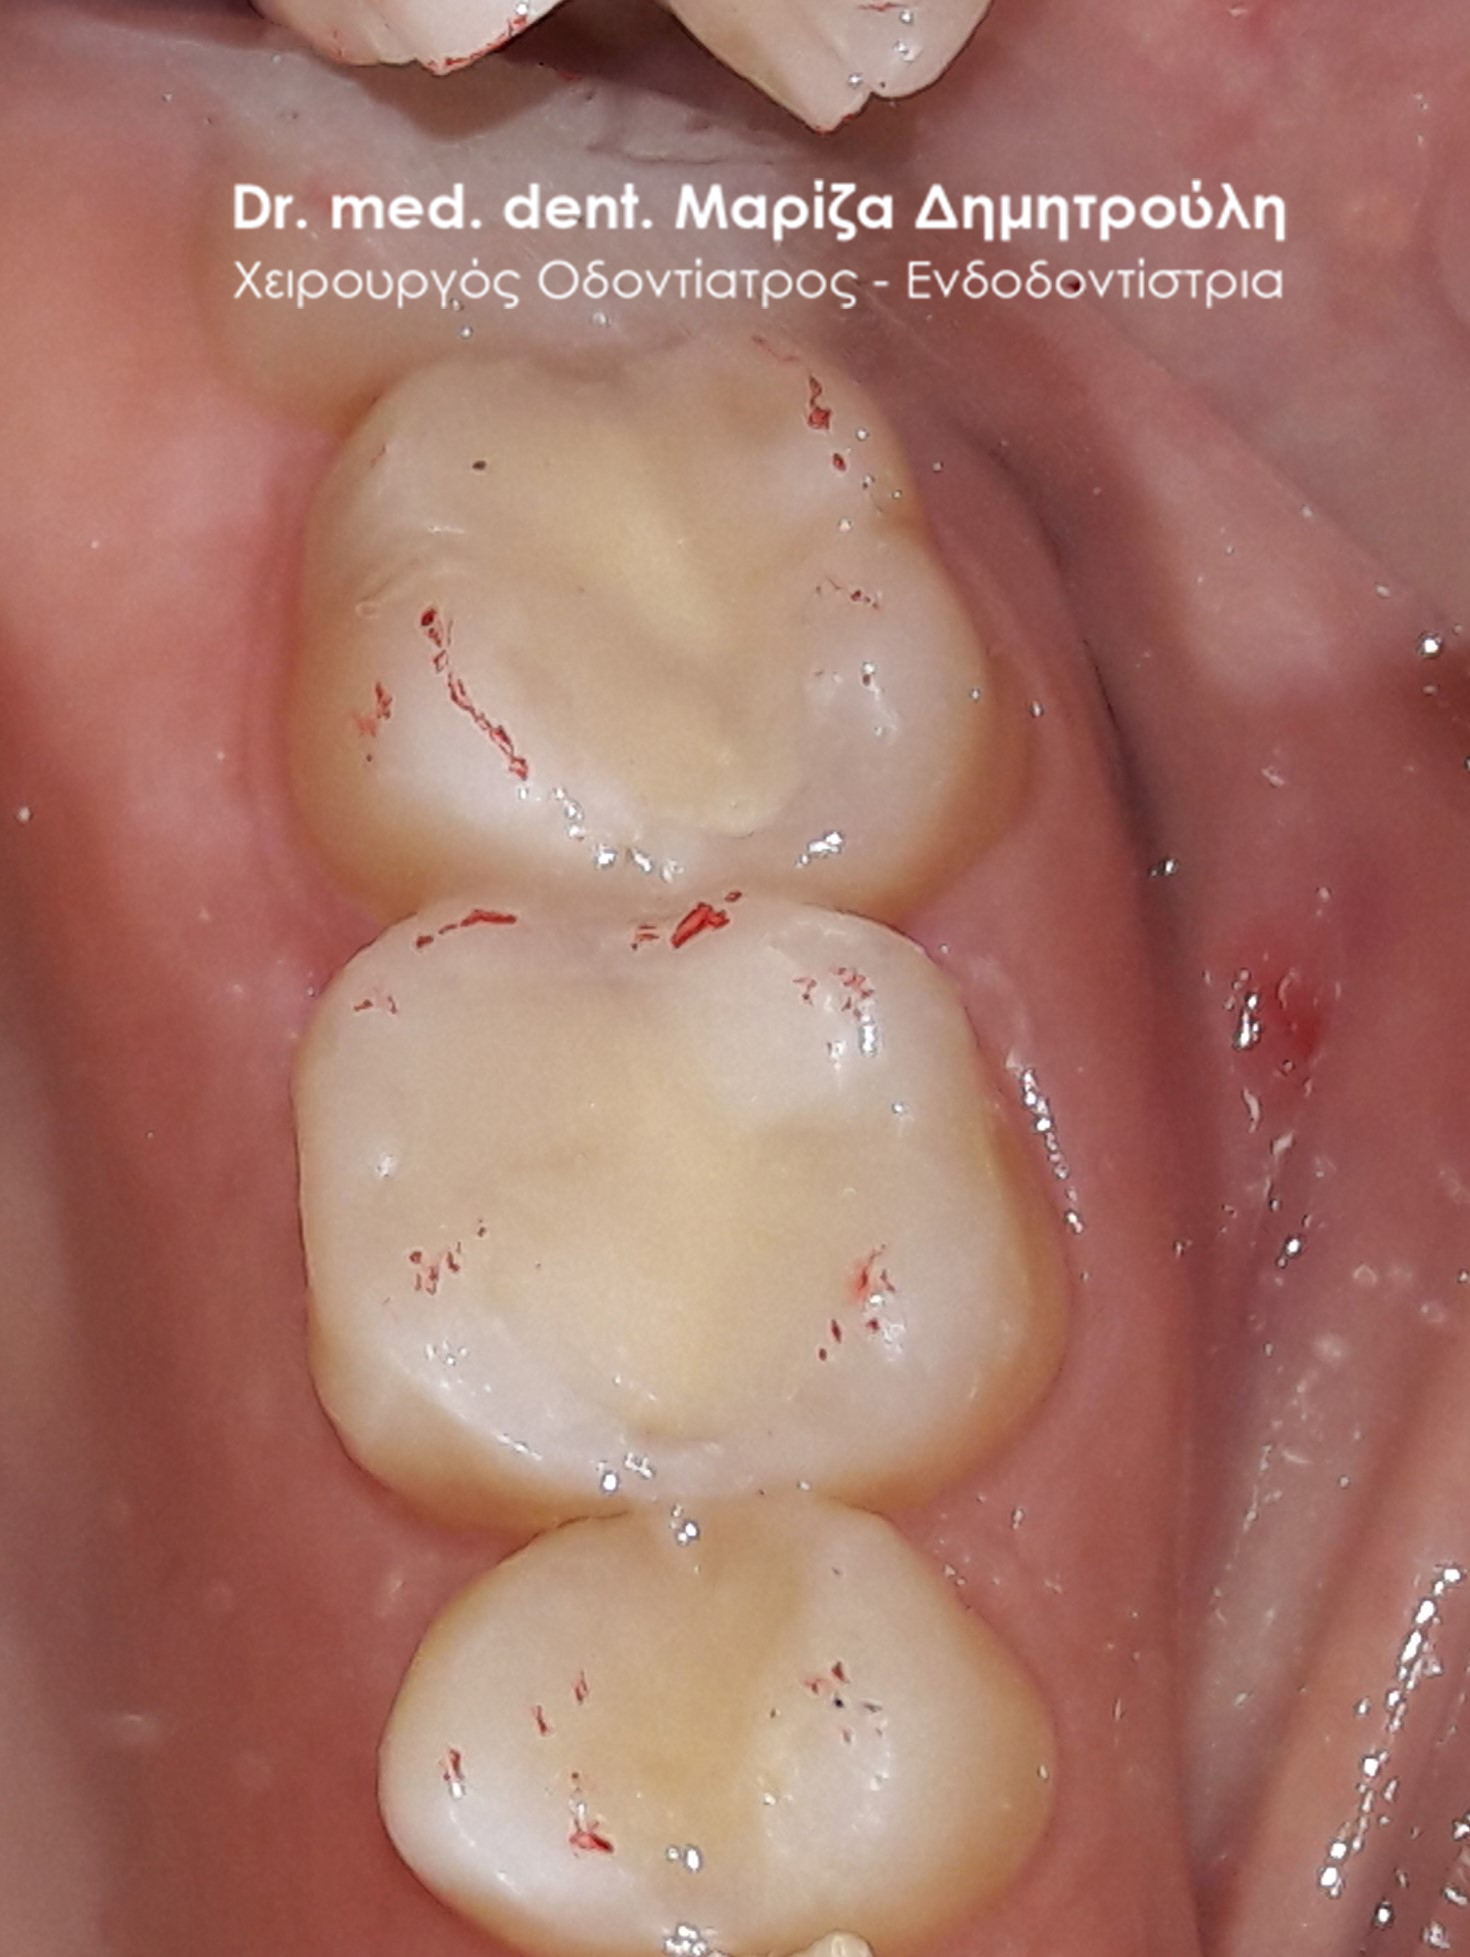

Περιστατικό – Αντικατάσταση σφραγισμάτων δοντιών

Ο ασθενής επιθυμούσε την αντικατάσταση των μαύρων σφραγισμάτων αμαλγάματος στον πρώτο δεξιό γομφίο και στο δεύτερο γομφίο με λευκά σφραγίσματα σύνθετης ρητίνης. Η θεραπεία πραγματοποιήθηκε με τη χρήση ελαστικού απομονωτήρα, όπως ορίζουν τα παγκόσμια πρωτόκολλα οδοντιατρικής για την αφαίρεση των μαύρων σφραγισμάτων. Όταν οι οδοντίατροι χρησιμοποιούν απομονωτήτρα κατά την αφαίρεση σφραγισμάτων αμαλγάματος, τότε ο ασθενής εισπνέει ελάχιστα και δεν καταπίνει τον υδράργυρο, που απελευθερώνεται κατά τη διαδικασία αυτή.

ΠΡΙΝ

META